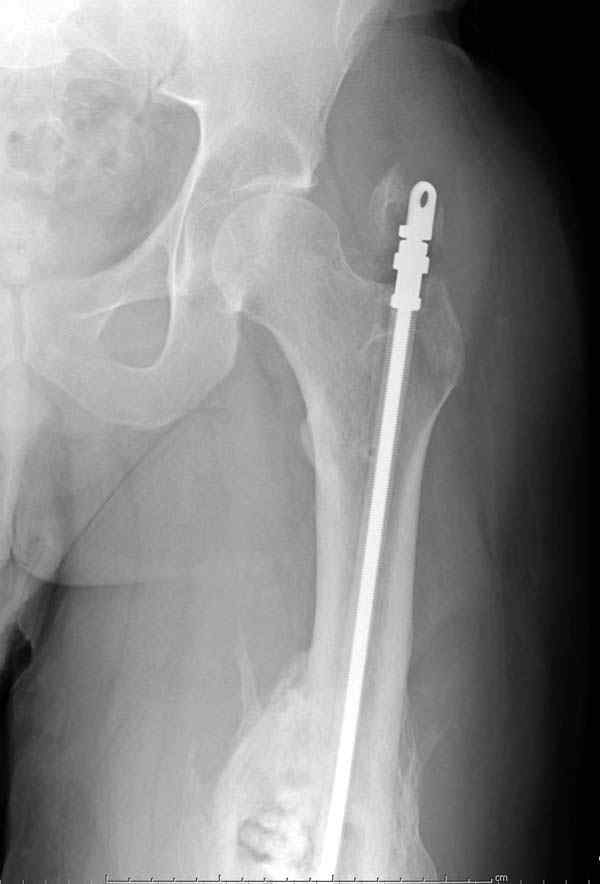

старый снтибиотический гвоздь

ренгенограмма инфицированного бедра со старым

антибиотическим гвоздем